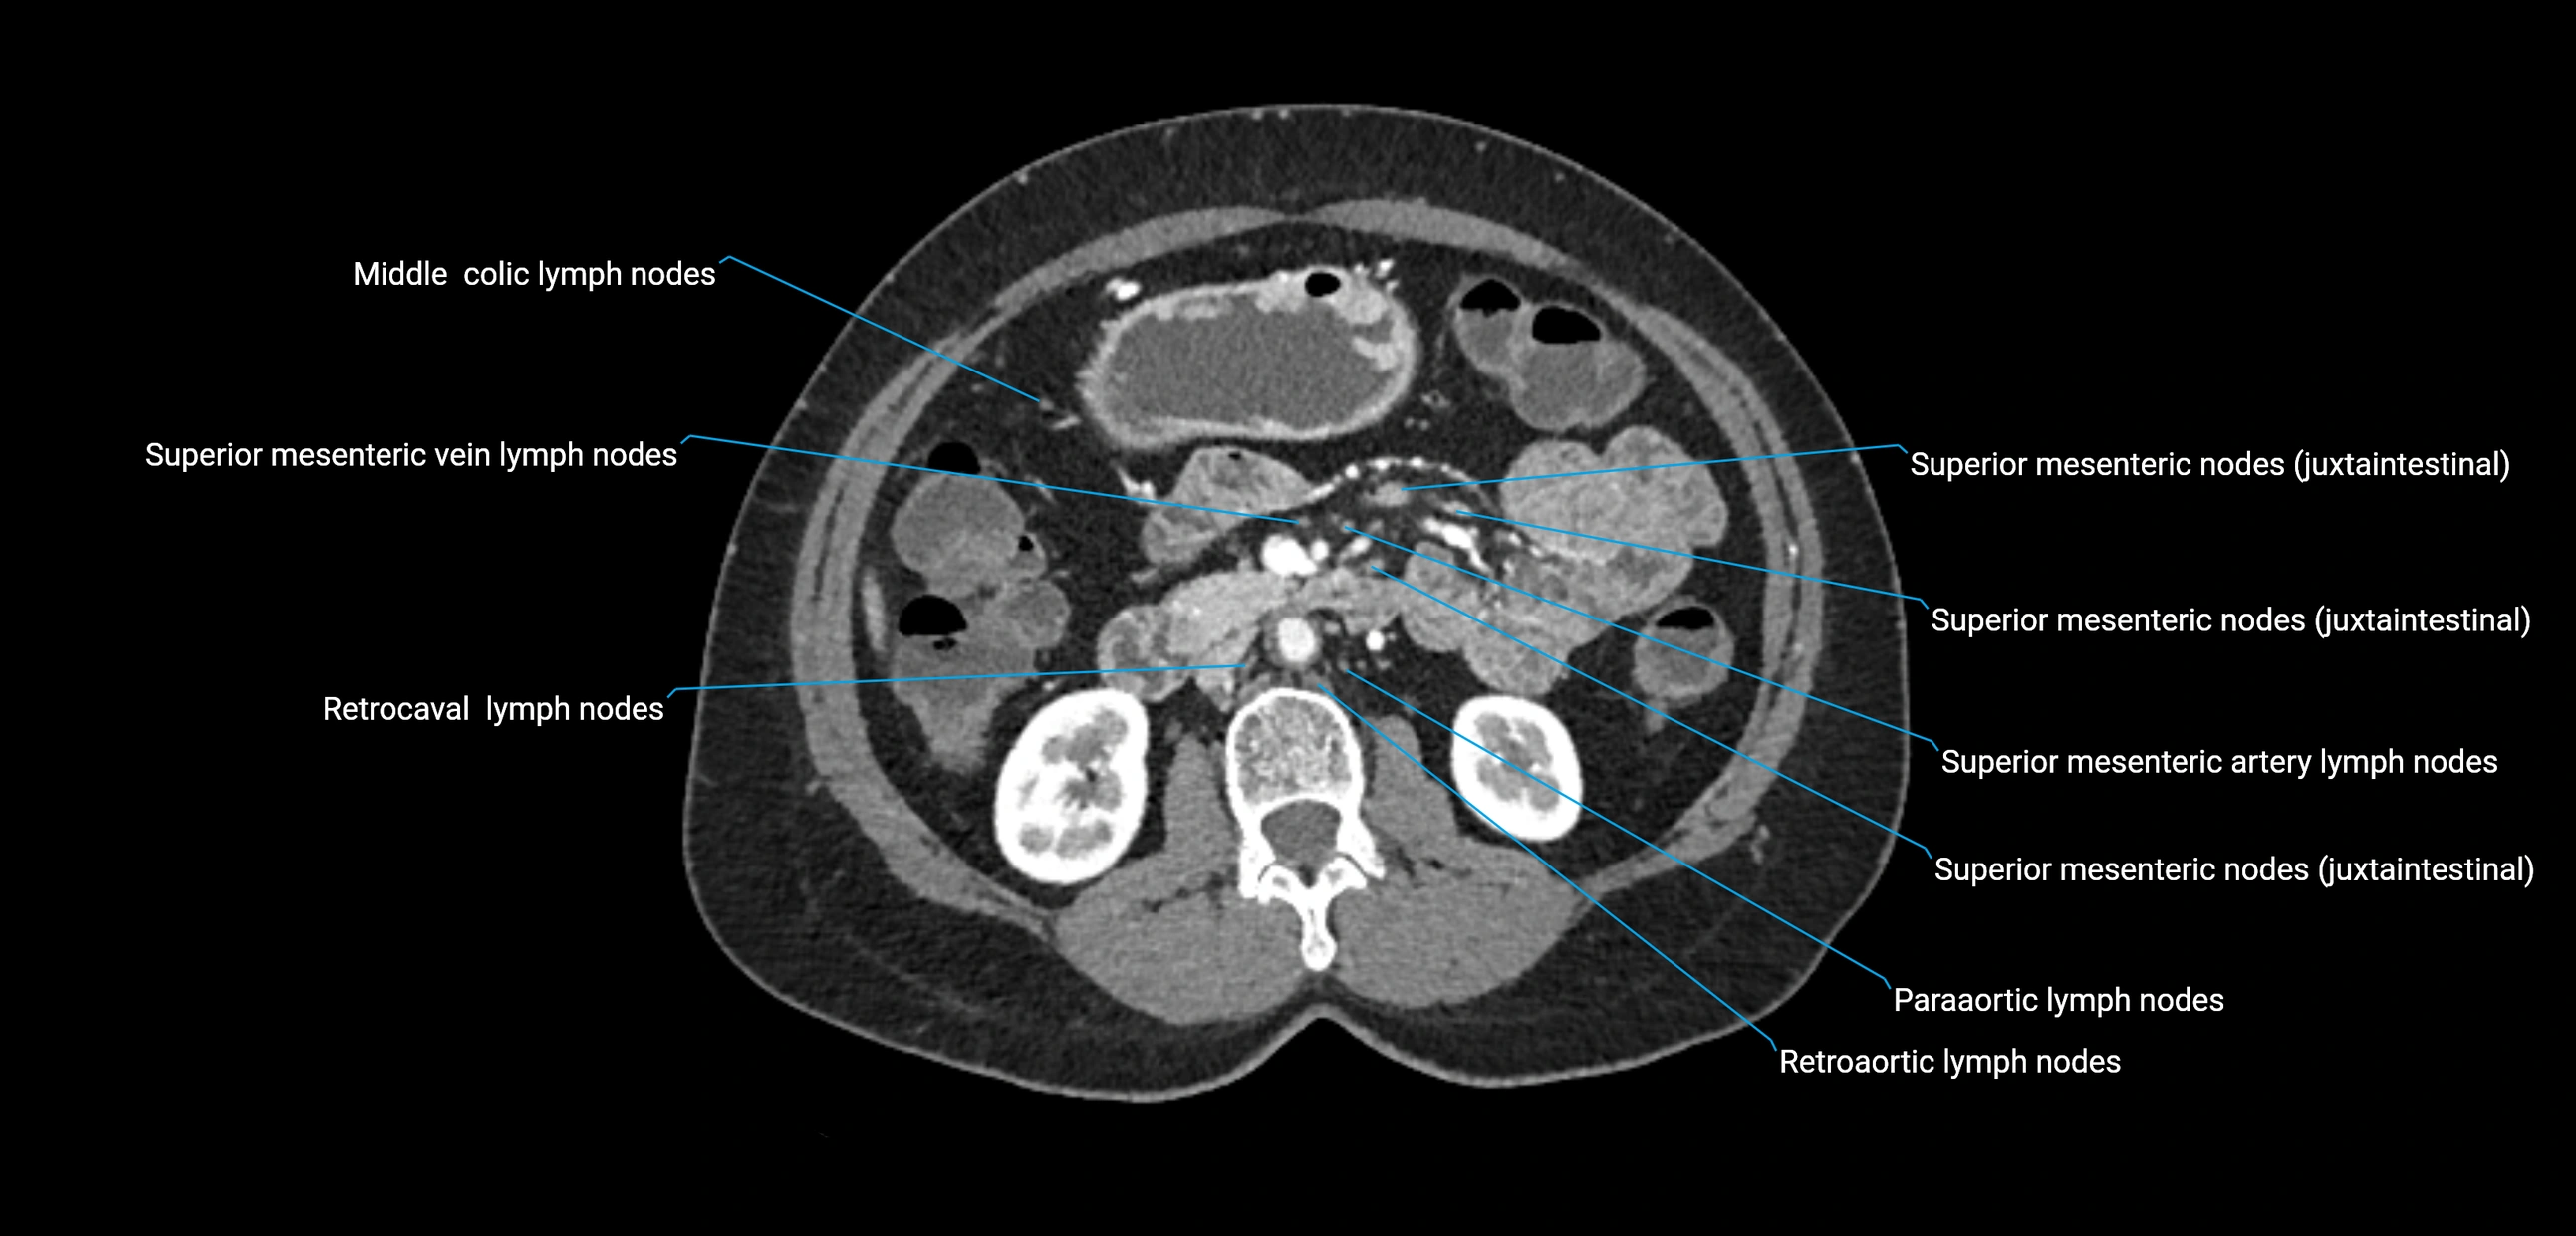

CT Appearance

CT Pre-Contrast:

• Nodes appear as soft-tissue density nodules adjacent to the aorta and IVC

• Calcification may be seen in chronic infections (e.g., tuberculosis)

CT Post-Contrast:

• Normal nodes enhance homogeneously

• Malignant nodes may show heterogeneous enhancement, central necrosis, or conglomerate formation

• Size >1 cm short axis is suspicious, though morphology and distribution are equally important